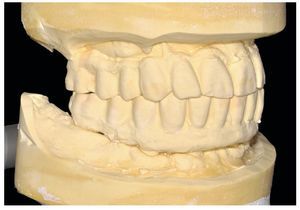

Fig. 83. Los modelos de las restauraciones prequirúrgicas montados en el articulador.

Fig. 84. El montaje cruzado del modelo maestro del maxilar superior, con duplicado debajo.

Fig. 85. El montaje del modelo maestro del maxilar inferior en el articulador.